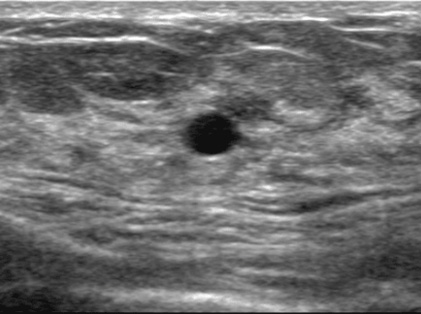

ㆍ유방 초음파 : 초음파를 이용하여 유방의 내부를 관찰하는 검사입니다. 유방을 압박하지 않고 검사할 수 있으며 통증이 없습니다. 또한, 유방의 모든 조직을 관찰할 수 있어 유방암의 조기 발견에 효과적입니다.

◆ 결절의 특징

1) 모양 : 불규칙하거나 찌그러진 모양의 결절은 암일 가능성이 높습니다.

2) 경계 : 경계가 명확하지 않고 주변 조직과 침범하는 형태의 결절은 암일 가능성이 높습니다.

3) 크기: 일반적으로 2cm 이상의 결절은 암일 가능성이 높습니다.

4) 성장속도: 빠르게 성장하는 결절은 암일 가능성이 높습니다.